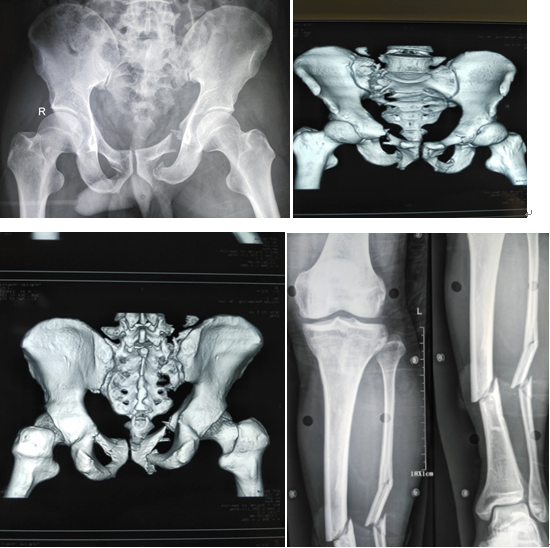

(2017-01-16)患者李某,男34岁,因双侧髋部、腰骶部及左小腿重物压伤6小时,由当地医院紧急转送至我院,入院后查体:双髋部及耻骨联合出肿胀、淤青、左小腿中下段胫前处可见一长约2.0cm开放性创口,活动性出血。骨盆挤压分离实验+,腰骶部及左小腿中下段均可及骨擦感,左足踇趾背伸激励减退,左踝及足背皮肤感觉迟钝。骨盆三维CT示:左侧骶骨、双侧耻骨上下支、坐骨支可见多发纵行骨折线影,断段移位。左小腿DR示:左胫腓骨中下段课件斜行骨折线影,对位欠佳。

入院诊断:1、双侧耻骨上下支骨折;2、双侧坐骨支骨折;3、左骶骨骨折;4、左侧胫腓骨中下段开放性骨折;5、腰5椎体右侧横突骨折。刘利主任医师查看患者,阅片后指示:患者直接暴力损伤致骨盆前环损伤,左侧骶骨呈新月形骨折,伴有左侧坐骨神经损伤,左胫腓骨中下段呈开放性螺旋形骨折,需行手术治疗。入院当晚即行左胫骨中下段开放性骨折切开复位+外固定架固定术。术后切口无感染。左下肢行骨牵引,待患者病情平稳后于伤后第8天行双侧耻骨上支及左骶骨骨折切开复位内固定术,手术方法引用了当今流行的骶骨后路切开复位,C臂透视下闭合打入骶髂关节拉力螺钉固定骶骨骨折;以及改良Stoppa手术入路治疗骨盆前环损伤。手术进行顺利,病人病情平稳。